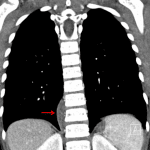

- Right paraspinal fusiform soft tissue density measuring 5 cm in craniocaudal dimension extending from T9-T10 through T12-L1

- Paraspinal mass (ganglioneuroma)

Right paraspinal fusiform soft tissue density measuring 5 cm in craniocaudal dimension extending from T9-T10 through T12-L1 concerning for a neoplasm. Recommend chest CT for further evaluation.